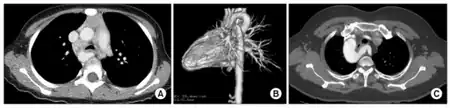

A vascular ring is a congenital defect in which there is an abnormal formation of the aorta and/or its surrounding blood vessels. The trachea and esophagus are completely encircled and sometimes compressed by a "ring" formed by these vessels, which can lead to breathing and digestive difficulties.[1][2]

Infants with vascular rings typically present before 12 months with respiratory or esophageal symptoms like stridor, wheezing, cough, dysphagia, or difficulty feeding. The stridor improves with neck extension, differentiating from laryngomalacia which is relieved by prone or upright positioning, and will not be relieved with corticosteroids or epinephrine, unlike croup. Diagnosis requires a high degree of clinical suspicion and can be confirmed with barium contrast esophagogram for those with esophageal symptoms, bronchoscopy, or CT or MRI.[3]